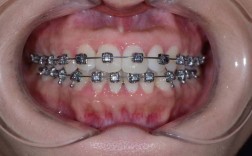

牙齿正畸治疗中,磨牙作为口腔中体积最大、咀嚼功能最强的牙齿,其位置、移动方向及稳定性对整个矫治效果至关重要,磨牙不仅承担着主要的咀嚼任务,还在维持咬合平衡、面部垂直高度及颌骨关系中发挥核心作用,正畸治疗中,无论是通过传统托槽矫治器还是隐形矫治器,磨牙的移动与调整往往是矫治计划的关键环节,涉及生物力学、解剖学及临床技术的综合应用。

正畸中磨牙移动的类型与临床应用

根据矫治目标,磨牙移动可分为近中移动、远中移动、垂直向压低、垂直向伸长及颊舌向调整等类型,每种类型对应不同的适应症与技术方法。